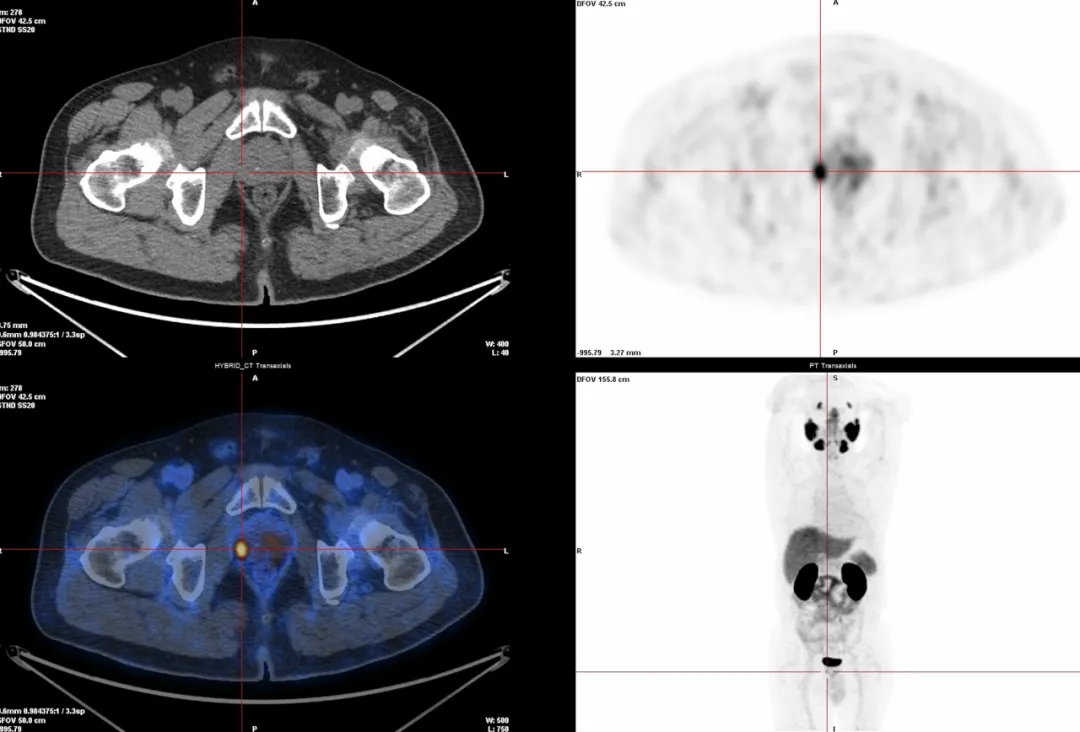

1. 前列腺癌检查(68Ga-PSMA):能更早发现肿瘤,判断是否扩散,还能帮助医生找到复发的位置,指导治疗和活检。

△前列腺癌微小原发灶检测